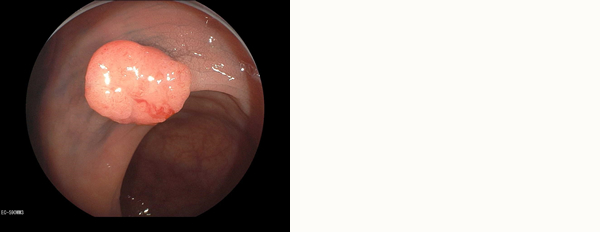

大腸ポリープ

色素を撒いたりし、ていねいな観察をすることでポリープがくっきり浮き上がってきます。

4mm程度の大きさであり、切除しました。